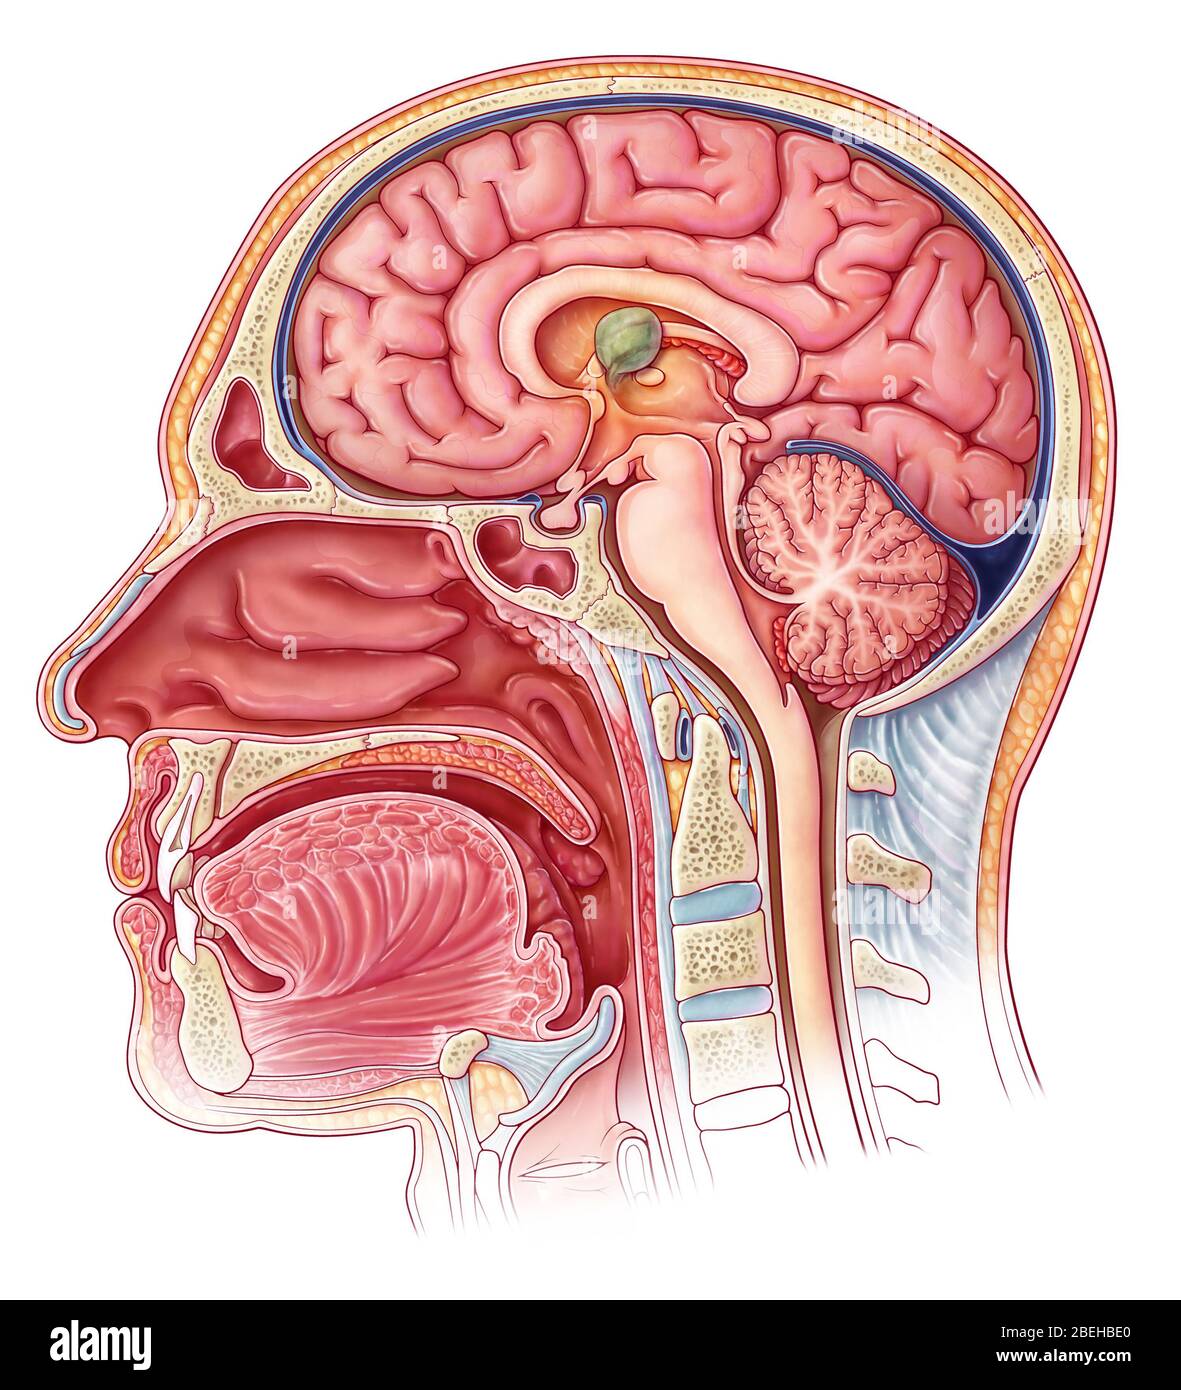

RM2ANEPH2–Die encyclopdia Britannica; ein Wörterbuch der Künste, Wissenschaften, Literatur und allgemeinen Informationen. Trakt. Der dritten Ventrikel (siehe Abb. 6) isa Hohlraum im mesialplane zwischen den beiden Optic thalami gelegen. Sein Dach ist durch die veluminterpositum und Körper der fornix gebildet; der Fußboden durch die posteriorperforated Raum, Korpora ajbicantia, Tuber cinereum, infundibulum und Optic commissure; seine vordere Begrenzung durch die anteriorpillars Der fornix, anterior Commissure und lamina cinerea; itsposterior Begrenzung durch den Corpora quadrigemina und posteriorcommissure. Den Hohlraum der Ventrikel ist o

RM2CDFE0C–. Elemente der physiologischen Psychologie; eine Abhandlung über die Aktivitäten und die Natur des Geistes, aus der physischen und experimentellen Gesichtspunkten. ide,die corpora quadrigemina. Die Kavität des Neuralrohres bleibt hier klein und bildet das Aquädukt, das den Viertmit dem dritten Ventrikel verbindet. Im Zwischenhirn dehnt sich das Aquädukt in den dritten Ventrikel aus; und hier wird wieder die dorsale Wand des Tubus zu einer breiten, dünnen Membran, die in den Ventrikel gefaltet und Blutgefäße mit sich trägt. Während die zerebralen Hemisphären ihr enormes Wachstum durchlaufen, dehnt sich die Kavität mit ihnen aus, andrema